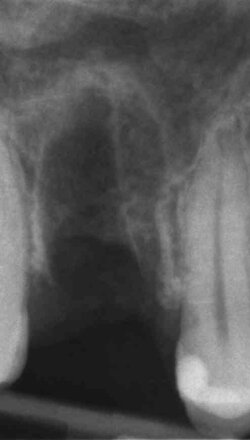

Implantologia Guidata: chirurgia mini-invasiva di alta precisione.